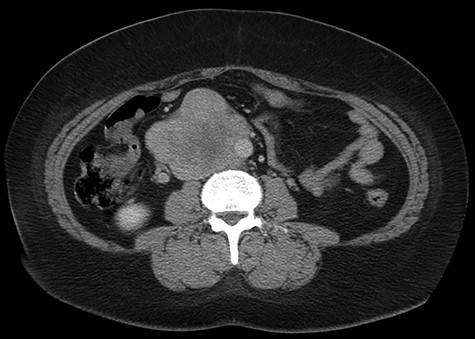

Abdominal CT scan demonstrating IVC lesion that partially encircles the aorta.

The patient had a body mass index of 40, so combined with her presentation, age and gender. The presumptive diagnosis was of gallbladder pathology, which prompted an abdominal ultrasound. Ultrasound revealed a large 7.7 × 6.3 × 7.2 cm heterogenous, hypoechoic masslike lesion overlying the IVC (Fig 1). Abdominal CT was performed, which revealed an 8.9 × 7.9 × 9 cm multilobulated, heterogeneous soft tissue mass in the right hemiabdomen, encasing the IVC and partially encasing the distal abdominal aorta (Figs. 2–4). CT-guided biopsy was performed, which revealed an LMS.